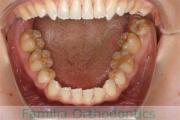

No.14V-516

- 主な症状:

- 上顎前突

- その他の症状:

- 叢生

- 年齢:

- 10歳

- 性別:

- 女性

- 抜歯部位

- 上:

- 44

- 下:

- 55

- 主な使用装置:

- FEA

- 治療にかかった費用:

- 90万円

きれいな歯並びにしたいということで来院されました。第一期治療で六歳臼歯の位置を維持する装置を入れて第二期治療の準備をしました。第二期は中学生になってから小臼歯を抜歯して行いました。二期治療は約2年半、25回程度の通院が必要でした。

二期治療開始前は叢生(でこぼこ、凹凸、ガタガタ)がかなりありましたので、保定をしっかりしないと段差ができてきたり後戻りのリスクがあります。